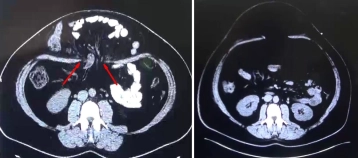

Na paciente jovem, uma hérnia maciça da parede abdominal se desenvolveu no pós-parto – sem intervenção abdominal prévia – o que levou ao deslocamento de segmentos do intestino grosso para o saco herniário (imagem de TC à esquerda com o orifício herniário marcado).

Em eventração avançada das vísceras através do defeito fascial, decidiu-se pré-operatoriamente condicionar a parede abdominal com um pneumoperitônio progressivo. Essa medida resultou em uma reposição espontânea completa do conteúdo do saco herniário.